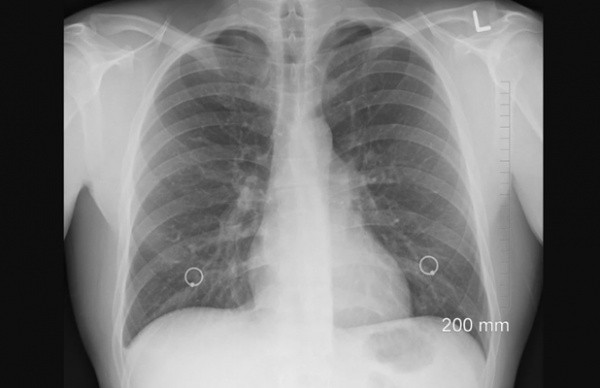

316-ти пациентам выставлен диагноз «пневмония», у 160 человек лабораторно подтверждена коронавирусная инфекция. 251 пациент находится в состоянии средней тяжести, 69 – в тяжелом. 204 человека нуждаются в поддержке кислородом, 20 пациентов подключены к аппаратам ИВЛ.

В Йошкар-Олинской городской больнице лечатся 135 пациентов с пневмонией. С лабораторно подтвержденной коронавирусной инфекцией (КИ) – 90. В тяжелом состоянии – 45 человек, в состоянии средней степени тяжести – 90, нуждаются в кислороде – 103, на искусственной вентиляции легких (ИВЛ) - 8.